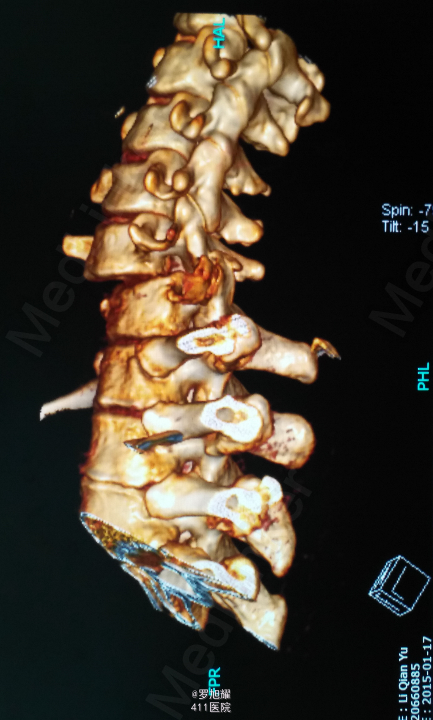

查体:双上肢前臂及以远感觉丧失,躯体自第二肋间平面以下感觉丧失。耸肩可,双侧三角肌、肱二三头肌肌力2级,腕关节屈伸、旋转及各指肌力0级。腱反射阴性,但球海绵体反射已经阳性。影像学检查示颈椎骨折脱位伴颈髓损伤。

诊断:颈6/7骨折脱位伴高位截瘫。处理:立即甲强龙冲击、脱水、保胃、营养神经治疗。首选治疗方案是颅骨牵引复位后前路融合固定,较后路稳定,出血也少,和家属谈话后开始颅骨牵引复位,4kg起步,每半小时增加1kg直至14kg,调整颈椎屈伸位,再加用手法牵引仍不能复位。改用备选方案,急诊行后路切开减压撬拨复位内固定,术后瘫痪症状部分改善。随访3月双上肢前臂及手部感觉恢复,仅双手掌尺侧及小指感觉障碍,双侧三角肌、肱二三头肌肌力4-5级,腕关节屈伸、旋转肌力左侧3级,右侧3-4级,但各指肌力仍0级。